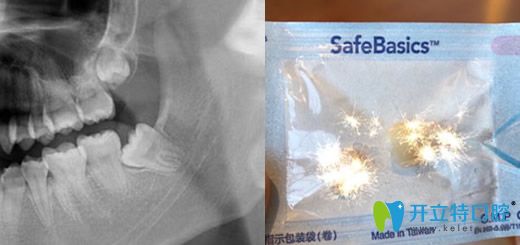

3、拔智齒

地點(diǎn):口腔朝陽(yáng)北路    醫(yī)生:趙曉嵐

顧客點(diǎn)評(píng):說(shuō)實(shí)話,為了正畸拔智齒真是使用了我所有的勇氣,差點(diǎn)讓我決定不做正畸了,后來(lái)還是硬著頭皮來(lái)啦,真的拔了感覺(jué)還好吧,術(shù)后被叮囑了好多注意事項(xiàng),服務(wù)非常贊,值得推薦。